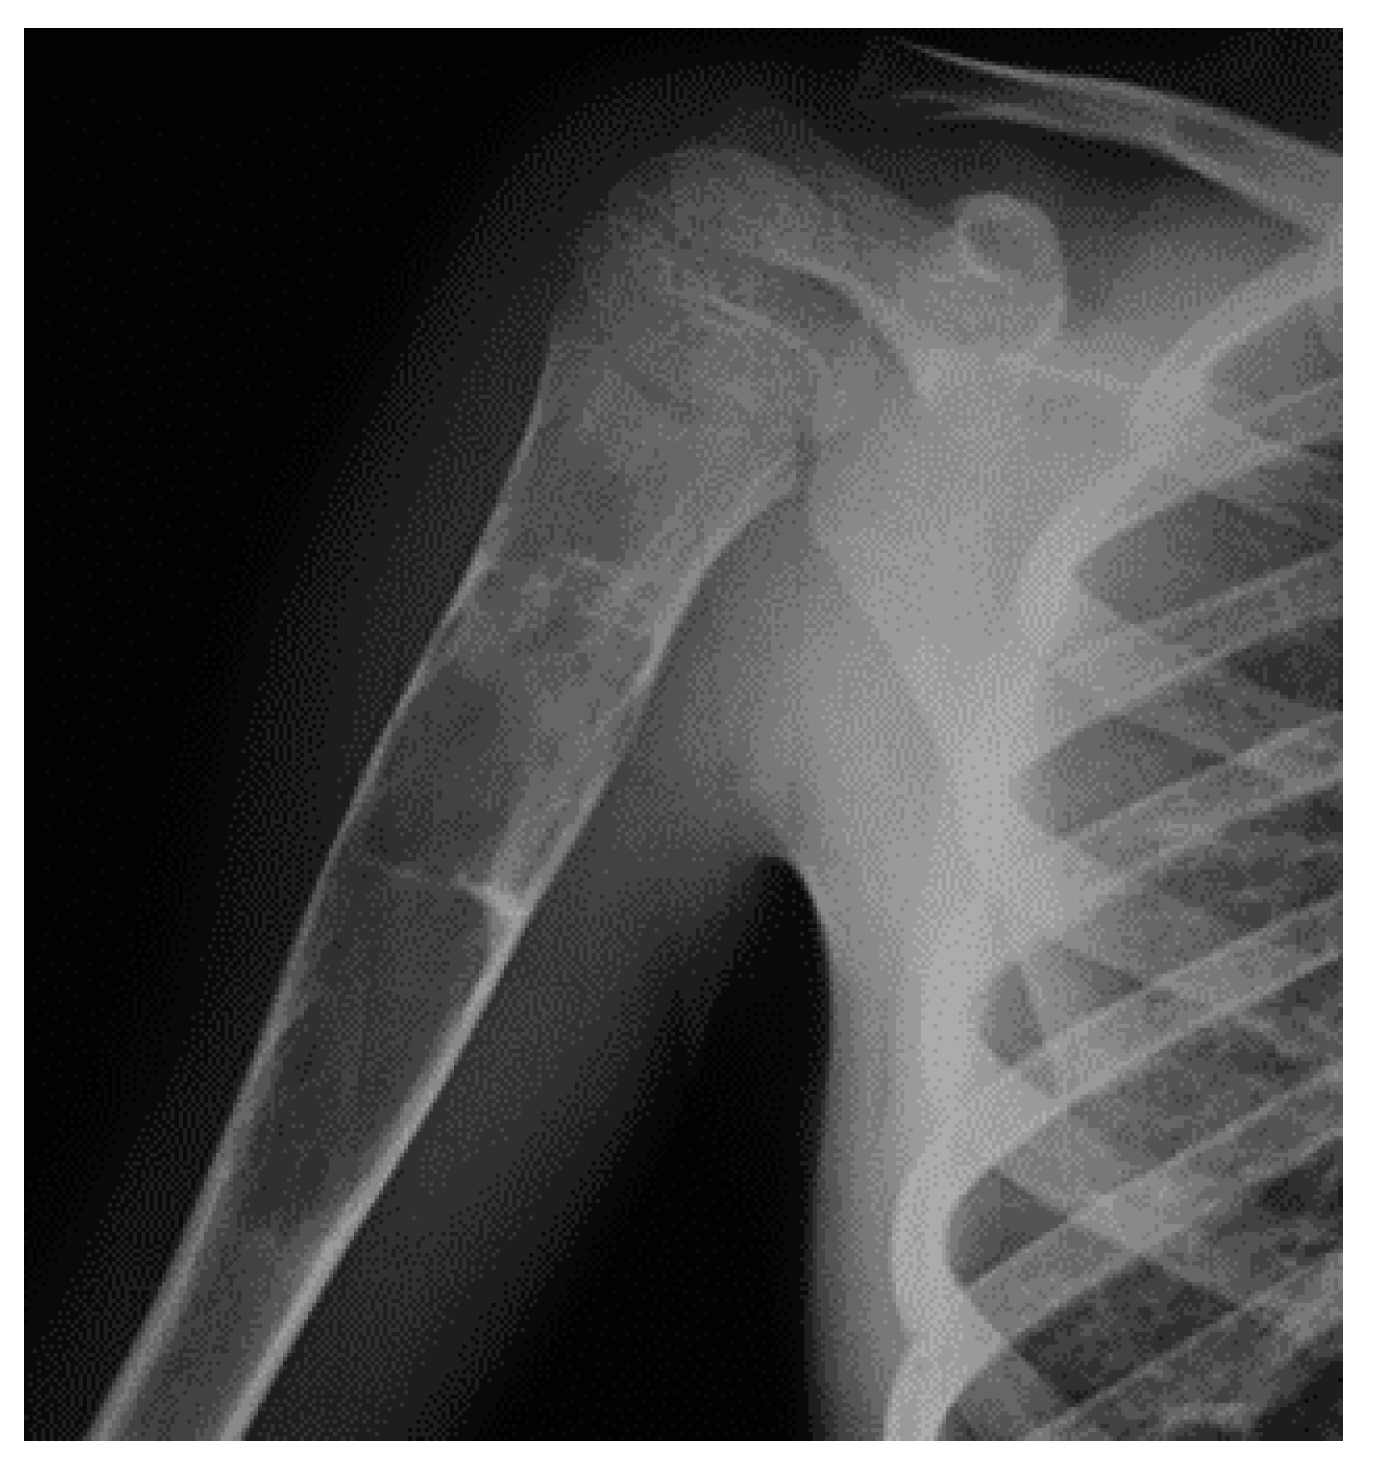

In both diseases, there is a higher risk of malignant transformation in chondrosarcoma (40%) [81]; in detail, the risk is 35% higher in Ollier disease and 50% higher in Maffucci syndrome. Histological features of both conditions include hypercellularity and cellular atypia (Figure 3).

Figure 3.

X-rays of a 10-year-old patient affected by Ollier syndrome.